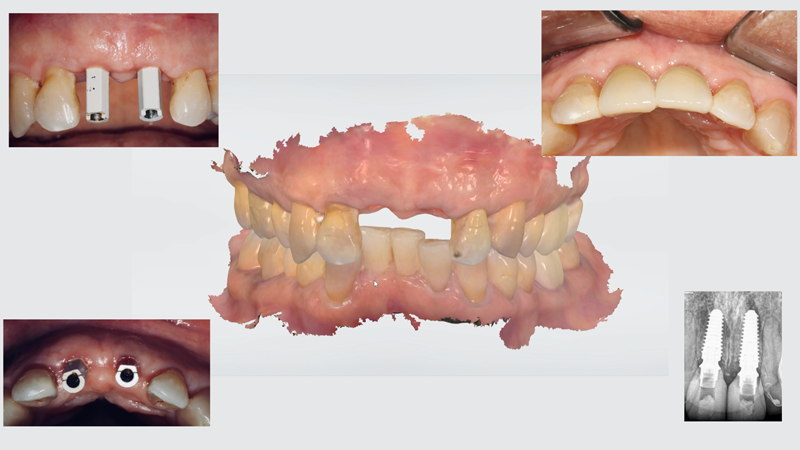

Case Study 3: Full-Arch Rehabilitation

Full-arch replacement can implement additional features of CBCT, such as extraoral facial scanning. Extraoral facial scanning can be integrated into CAD/CAM software, thereby replacing the use of inaccurate 2-dimensional images with 3D representations to determine lip position, vertical dimension, and smile line, among other facial parameters.

A 66-year-old male patient presented to the clinic with failing maxillary dentition. Along with a plan to address the extensive decay and tooth mobility, the patient expressed a desire for a cosmetic outcome. Treatment options included extractions with implant placement, extractions with removable prostheses, and periodontal maintenance with a guarded long-term prognosis. The patient elected to undergo extraction of his maxillary teeth, with implant placement and a fixed full-arch prosthesis (All-on-X).

An All-on-X treatment approach for a patient requiring full-arch rehabilitation involves a number of considerations with regard to fixed restorative options. Fixed restorative options include FP1 - tooth replacement only; FP2 - tooth elongated or slight pink replacement; and FP3 - tooth and tissue replacement.21 FP3 requires significant bone reduction to create the restorative space required to simulate both tooth and tissues. While FP3 is easier to accomplish, the amount of bone reduction required would potentially jeopardize the esthetic outcomes desired by the patient. FP1 may allow a better esthetic appearance, but the results can be difficult to achieve; without controlling the amount of bone reduction required for restorative space, the outcome may head from an FP1 to an FP2/3. Utilizing the advanced tools of the CS MAR along with IOS and facial scanning using CS 9600 (Carestream Dental; alternatively: RAYSCAN Studio, Ray America; Viso® G7, Planmeca) (Figure 13), a proper 3D simulation was created and a plan for the full-arch rehabilitation was developed. For this patient, the plan included incorporating partial extraction therapy for buccal plate preservation and fabrication of a scalloping guide to control the restorative and esthetic space.

Fig 13. 3D facial scanning acquired from CBCT. Planning software

allows for advanced planning and smile design.